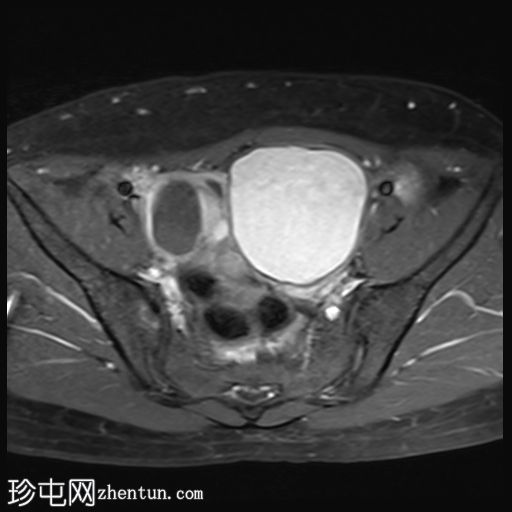

脂肪抑制像

轴位

5.jpg

左侧卵巢可见一巨大、无强化囊性病变。该病变壁薄,在T1加权像和T1脂肪抑制像上呈均匀高信号,在T2加权像上呈独特的阴影状,符合子宫内膜异位囊肿的特征。值得注意的是,该病变可见两个增强灶,但未见内部实性成分或对比增强。

此外,右侧卵巢内数个小的、无强化囊性病变表现出类似的信号特征,这也符合子宫内膜异位囊肿的特征。

双侧卵巢向内侧移位,形成“接吻卵巢征”。